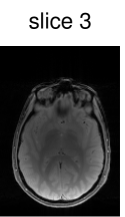

The CAIPIRINHA-based modifications to the SMS pulse design (see Fig. 1(c)) are illustrated in Fig. 5 (showing the case of five slices for the sake of variation). Figure 5(a) shows the unmodified pulse, which differs in structure from the cases with an even number of slices in, e.g., Fig. 4(c) due to the different symmetry of the slice profile (see Fig. 5(b)). On the other hand, the pulse is very similar to the modified pulse for the alternating phase shift; see Fig. 5(c) for the computed pulse and Fig. 5(d) for the resulting slice profile. For illustration, a slice-aliased reconstruction of the acquired in-vivo data using this pulse sequence is shown in Fig. 5(e).

z readout

sG reconstruction

Figure 6 shows the image reconstruction using optimized RF pulses for simultaneous excitation of two, four and six slices with the same slice separation and thickness as above. As can be seen clearly in the first column, all three pulses lead to the desired excitation pattern in-vivo as well. The remaining columns show the slice-GRAPPA reconstructions, which illustrate that the excitation is uniform across the field of view.